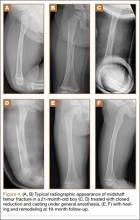

All fractures united without cast revision. Mean cast time was 4.5 weeks (range, 16 days–6 weeks). Immediate postoperative alignment was 2.5° varus (range, 11° valgus to 16° varus) and 7° procurvatum (range, 1° recurvatum to 22° procurvatum). Mean shortening was 1.5 cm (range, 0-2.7 cm). Final alignment was 1° valgus (range, 9° valgus to 12° varus) and 5° procurvatum (range, 0° to 22°). Mean follow-up was 8 months. There were no cases of skin maceration or cast failure. No casts precluded use of a spica car-seat. Figure 4 shows a typical case with a midshaft fracture treated with closed reduction and casting for 4 weeks with good remodeling at final follow-up, 19 months after injury.